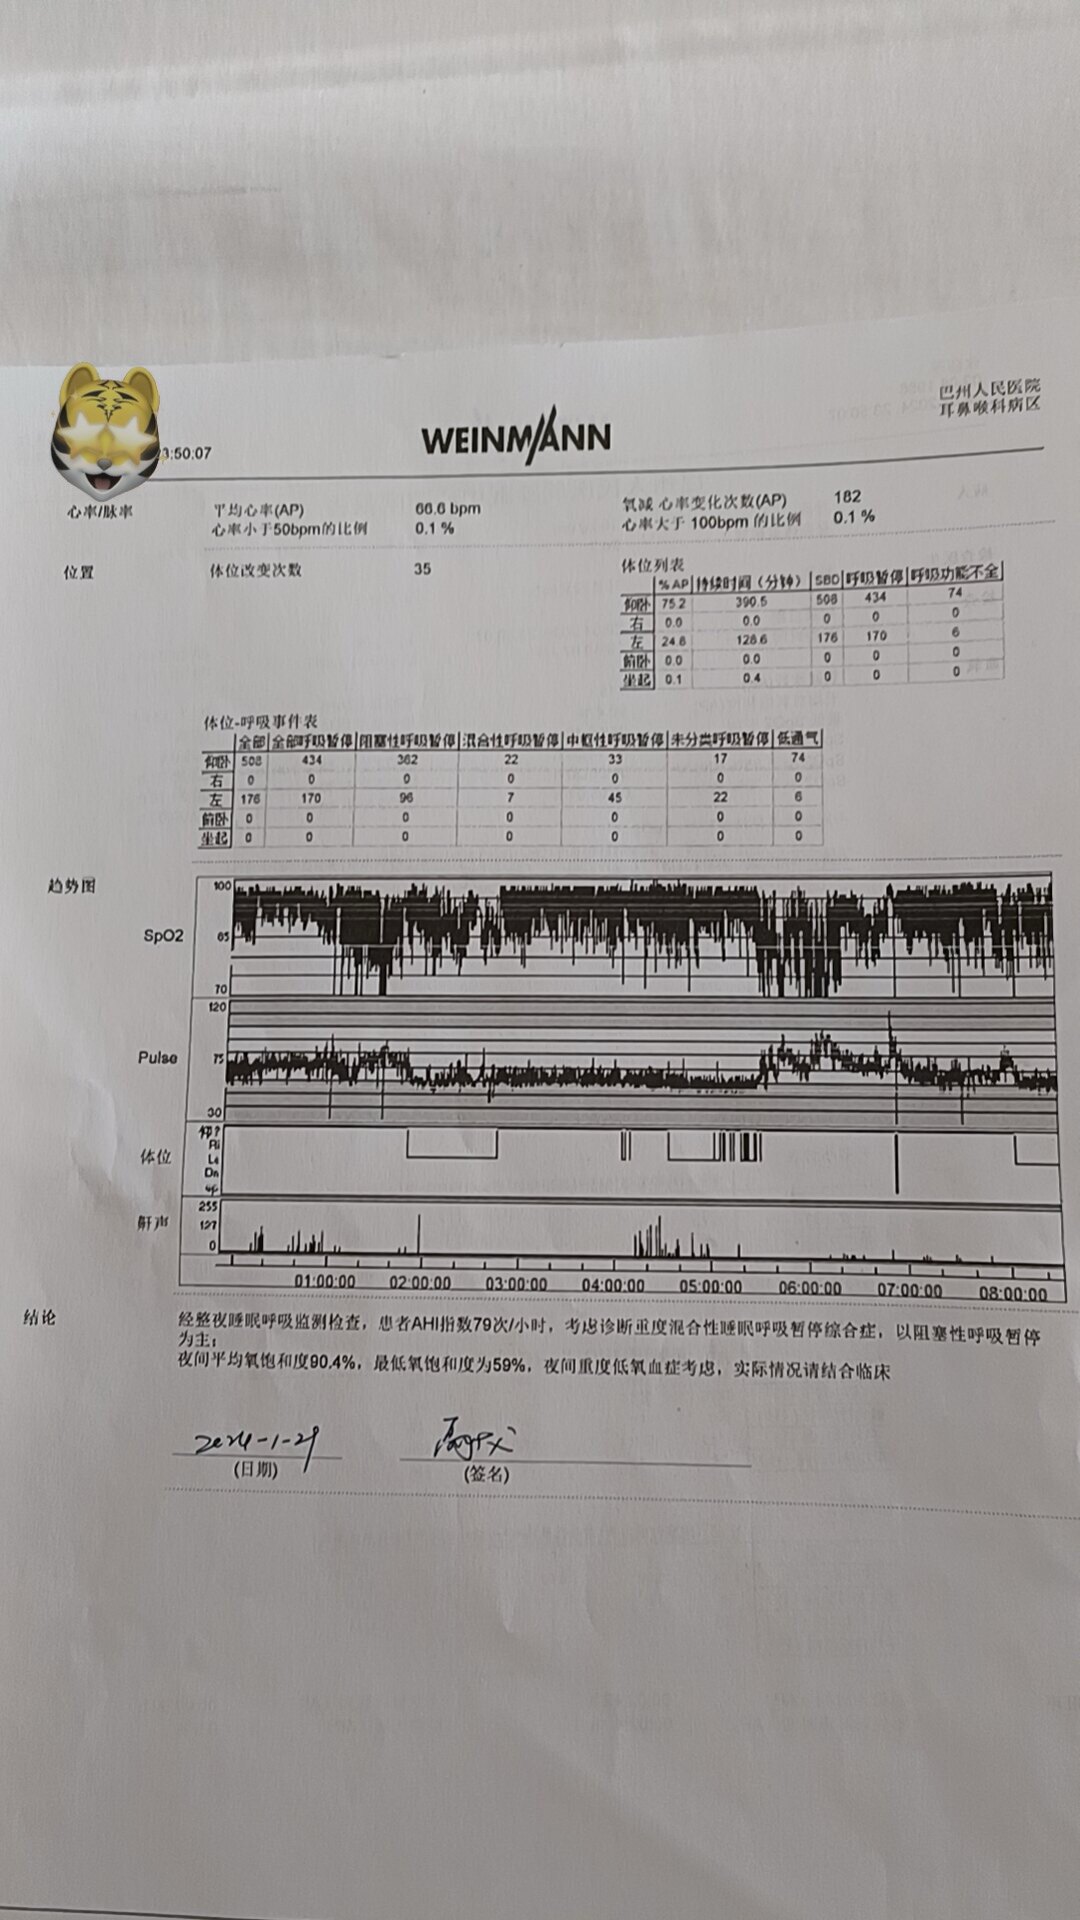

之前同一天做过“鼾症兄弟”、“鼾症兄妹”和“鼾症父女”,这是第一次给“鼾症母女”同一天手术。这对母女来自新疆巴音郭楞,重度鼾症父亲37岁,因为扁桃体肥大,自小打鼾,4年前产后打鼾加重,伴夜间憋醒,严重影响睡眠,当地医生建议患者戴呼吸机,但是她无法耐受呼吸机。电话咨询后,下定决心来广州找我手术。同时她也把4岁女儿打鼾和张口呼吸的情况也详细告诉我,鼾症女儿因为扁桃体3度肥大,腺样体堵塞后鼻孔2/3,造成张口呼吸,对于这样的孩子,一定需要早点手术干预,不然会影响面部发育和生长发育,甚至智力发育。所以我就让她们母女一起来广州找我手术。手术时发现母女俩的扁桃体肥大,因为女孩子4岁,我常规保留双下极扁桃体的1/5和腺样体的1/5。希望母女手术后身体早日恢复正常!有一个安稳的睡眠质量,健健康康的生活!